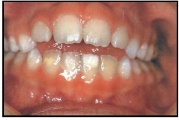

Valehambumus

Hammaste asendianomaaliad on tingitud tavaliselt arenguhäirest.

Sümptomid:

probleemid kõnega

(5)

probleemid neelamisega

(4)

suuhingamine

(6)